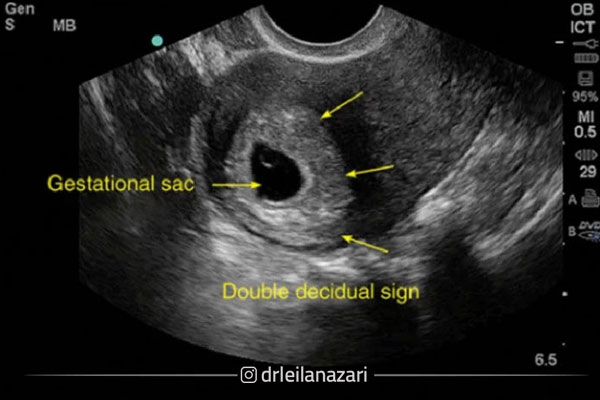

شاید برایتان جالب باشد اگر بدانید در اکثر موارد خانم ‌ها بدون اینکه متوجه بارداری پوچ خود شوند، آن را از دست می‌دهند؛ به همین دلیل است که بیشتر این مشکل ناشناخته باقی می ‌مانند. متاسفانه در سال ‌های اخیر بارداری پوچ رایج شده است و در گذشته احتمال بروز این اتفاق پایین‌ تر بود. نحوه تشخیص بارداری پوچ از طریق آزمایش و سونوگرافی و با نظر پزشک متخصص امکان ‌پذیر است.